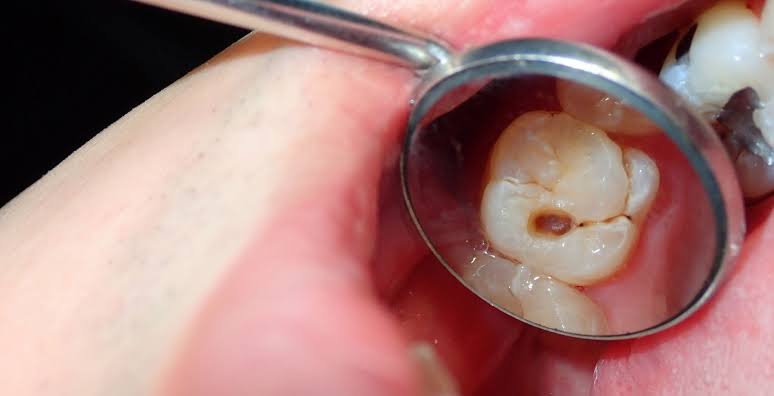

कैविटी आमतौर पर दांतों की सड़न का नतीजा होती है, जिसका इलाज न किया गया हो। आपके दांतों की सुरक्षा एक सख्त बाहरी परत करती है, जिसे ‘इनेमल’ कहते हैं। यह परत दांतों को रोज़ाना के घिसाव और बैक्टीरिया की गतिविधियों से बचाती है। जब प्लाक बैक्टीरिया आपके खाने में मौजूद चीनी (शुगर) को खाते हैं, तो वे ऐसे एसिड बनाते हैं जो धीरे-धीरे इनेमल को गला देते हैं।

जैसे-जैसे इनेमल कमज़ोर होता है, उसमें एक छोटा सा गड्ढा या छेद बनने लगता है। समय के साथ, यह खराबी बढ़ सकती है, जिससे दांतों में सेंसिटिविटी (झनझनाहट), दर्द, इन्फेक्शन और दांतों से जुड़ी दूसरी समस्याएं हो सकती हैं। कैविटी को बढ़ने से रोकने और अपने दांतों की सेहत बनाए रखने के लिए तुरंत ध्यान देना और दांतों की सही देखभाल करना बहुत ज़रूरी है।